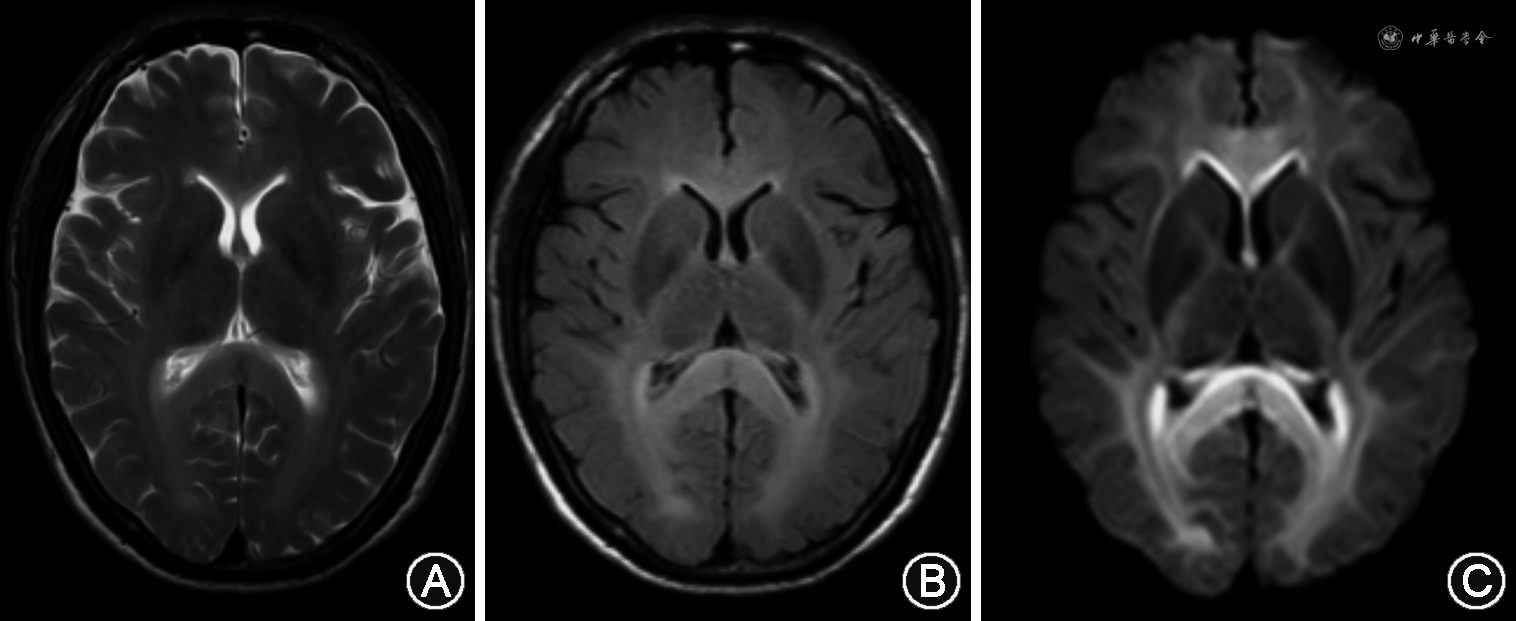

本患者口服虫螨-茚虫威20 ml后,出现发热、出汗及截瘫等症状,期间未出现呼吸困难、口唇黏膜、甲床紫绀等症状,据临床表现推测其可能为虫螨腈中毒,原因如下:首先,虫螨-茚虫威混合制剂中茚虫威浓度远远低于虫螨腈;其次,茚虫威的毒性明显小于虫螨腈且茚虫威具有低哺乳动物毒性的特点[18]。本患者中毒后血磷酸肌酸酶、乳酸脱氢酶、肝酶基本恢复正常,仅遗留截瘫,表明重要脏器(如肝脏、肌肉)等基本不受影响,以神经系统损害为主;结合肌电图提示周围神经未见明显异常,因而损害主要为CNS。根据影像学证据,经复习文献,目前仅见4例人类虫螨腈中毒并累及CNS报道,MRI均表现为长T1长T2,液体衰减反转恢复(FLAIR)序列、DWI高信号,表观弥散系数(ADC)低信号的双侧大脑半球白质束对称性病变及全脊髓弥漫性肿胀[7, 8,19,14]。本患者头颅MRI(图1)在T2WI上突出表现为广泛性和对称性的高信号改变伴明显弥散受限,其异常信号局限于整个大脑、脑干的白质及脊髓MRI(图2),提示胸髓可疑肿胀,与既往报道的虫螨腈中毒并累及CNS的影像结果非常相似。综上所述,本患者虫螨-茚虫威中毒后的临床症状、影像学特点均与既往病例报道的人类虫螨腈中毒的临床影像表现相符,因此最终考虑其为虫螨腈中毒。

人类虫螨腈中毒易导致CNS白质病变的机制目前尚不清楚,推测原因如下:首先,虫螨腈属于较强的脂溶性亲神经毒物,容易透过血脑屏障;其次,虫螨腈影响细胞能量代谢,且CNS本身代谢旺盛,能量消耗大,因此CNS比人体其他组织更易受虫螨腈的干扰;再次,与CNS的灰质相比,白质更容易受亲脂类毒素的破坏[20],因此最终虫螨腈中毒累及神经系统以广泛CNS白质病变为主。CNS白质病变常见的病理改变为脱髓鞘[21],本患者脑脊液及血清脱髓鞘抗体水通道蛋白4-IgG、髓鞘少突胶质细胞糖蛋白-IgG、神经胶质纤维酸性蛋白-IgG、IgG-寡克隆区带均为阴性,暂时能排除其CNS白质病变为原发性免疫介导的CNS炎性脱髓鞘。近来de Oliveira等[22]总结了常见中毒代谢性脑病的影像学特点,发现不累及灰质的弥散受限、非强化的弥漫性对称性脑白质病灶多数是可逆的,其病理改变可能为髓鞘内水肿。Baek等[14]报道了1例口服极少量10%的虫螨腈19 d后出现截瘫,MRI呈FLAIR、DWI高信号,ADC低信号且非强化的双侧对称性弥漫脑白质病变以及全脊髓肿胀的幸存患者,中毒71 d后其MRI表现为脑及T7以上脊髓异常信号完全消失,T7以下脊髓残留高信号及萎缩改变;该患者CNS白质异常信号消失的特点表明虫螨腈中毒性CNS白质病变可逆。同时也有研究者对虫螨腈中毒后的大鼠神经组织行病理活检,发现其神经髓鞘轻度肿胀[14]。由此可见,虫螨腈中毒性CNS白质病变极有可能为可逆性髓鞘内水肿。本例患者虫螨腈摄入剂量、截瘫的临床症状以及MRI特点均与Baek等[14]报道的虫螨腈中毒患者十分相似,因此推测其虫螨腈中毒性CNS白质病变为可逆性髓鞘内水肿。遗憾的是,由于经济条件受限,本患者出院后拒绝复查MRI,其中毒后第8天和第19天的MRI检查结果提示异常信号未消失,可能由于复查MRI的间隔时间过短。随访至今本患者仍遗留截瘫症状,推测可能与MRI提示T9椎体平对脊髓片状强化、不可逆损害有关。本例患者与Baek等[14]报道的患者虫螨腈中毒后分别出现T9、T7脊髓的不可逆病灶,表明胸髓比其他脊髓节段更易受毒物影响,推测可能与胸髓血供较其他脊髓节段稍差有关。